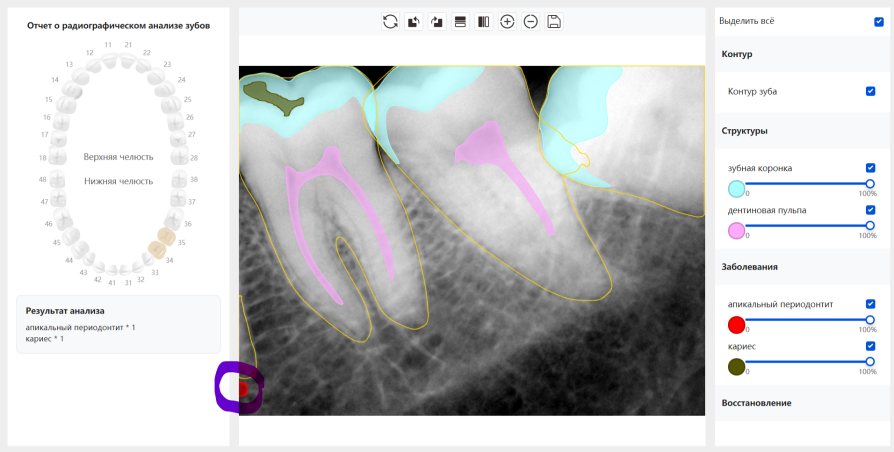

CR/DR 牙齿分割阶段记录

当前进展

- 完成了 CR/DR 牙齿相关分割训练

相关测试

遇到的问题

- 训练过程中出现过 mask 下移问题

- 部分结果会出现 box 填充异常

- mask 边缘仍然有比较明显的锯齿感